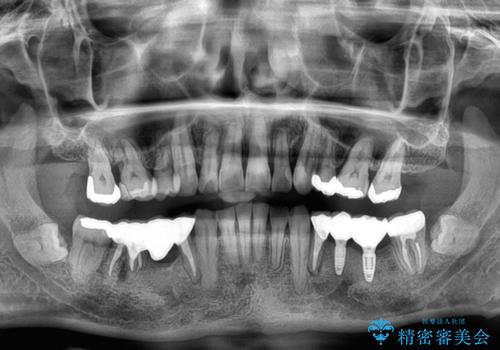

奥歯の欠損と前歯のデコボコを治したい インプラントと矯正治療の総合歯科治療

- 下顎両側の欠損と上顎前歯のデコボコを気にして来院された患者様です。

デコボコは今まで気にせずにいたそうですが、奥歯の欠損改善を機に、矯正治療に興味があるので、相談したいとのことでした。

奥歯に欠損が多く、矯正治療はやや難航することが予想されますが、患者様の希望もあり、上顎左右小臼歯を1本ずつ抜歯し、ワイヤー装置にて矯正治療を行うこととしました。

矯正歯科治療を行うに当たり、痛みや違和感を感じている歯の根管治療を行い、矯正治療中にインプラント埋入し、補綴治療と矯正治療を同時に終了できるように進めて行くこととしました。